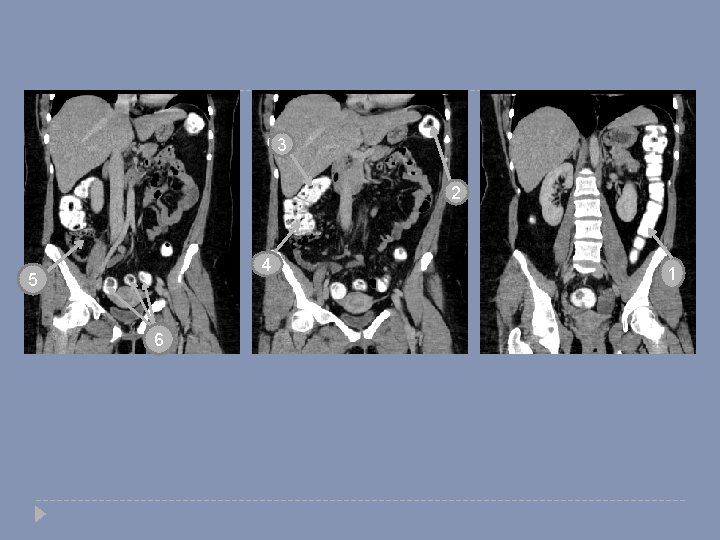

3 2 4 5 6 1

3 2 4 5 1 6 Descending colon Splenic flexure Hepatic flexure Ascending colon cecum Sigmoid colon . 1. 2. 3. 4. 5. 6